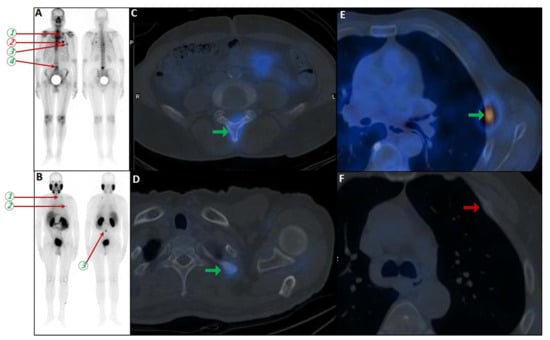

6.3. False Negatives Due to Heterogeneous PSMA Expression

False-negative findings in PSMA PET/CT can occur due to heterogeneous PSMA expression and partial volume effects, particularly in castration-resistant prostate cancer (CRPC) patients with small-volume rib metastases [145,146] and rarely in the staging scenario [147] (Figure 5). As highlighted by Serani et al., diminished PSMA expression in CRPC may obscure metastatic lesions, reducing detection sensitivity. In support, Simsek et al. reported that 1.4% of 68Ga-PSMA-11 scans failed to identify existing metastases due to this limitation [100,132].

Figure 5.

PSMA scan ruling out the possibility of metastatic prostate cancer. A 73-year-old man was referred for diagnosis/staging, due to mildly elevated serum PSA levels, and a few lytic–sclerotic bone lesions incidentally found in the recent abdominopelvic CT scan. Whole-body 99mTc-PSMA (A,B) and SPECT/CT (C) showed faint PSMA uptake in the prostate gland (PRIMARY score 1) with multiple non-PSMA-avid (white arrows) lytic–sclerotic changes in the L4 vertebra (D), sacrum (E), left iliac (F) and left 6th rib (G). No nodal or visceral involvement was evident. These bone lesions were finally concluded as unrelated pathology to prostate cancer, yet the rare possibility of non-PSMA-avid tumor could not be entirely ruled out.

Additionally, treatment-induced modulation of PSMA expression, as noted by both Simsek et al. and Rizzo et al., complicates post-therapy imaging interpretation, especially in patients undergoing hormonal or systemic therapies. These false negatives carry the risk of underdiagnosis, which may result in delayed initiation of critical interventions in patients with true metastatic progression [8,100,148].